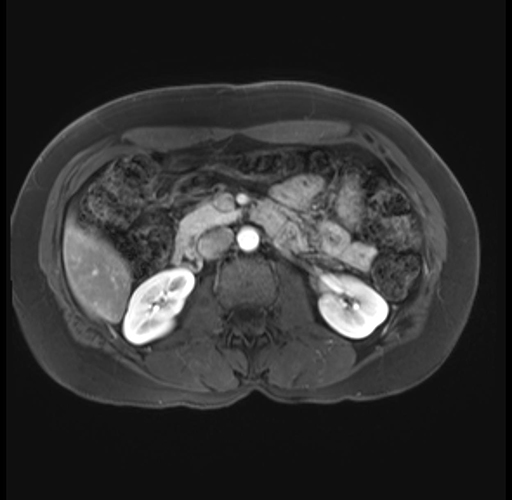

Imaging Analysis

Look through the patient's CT scan to identify any areas of concern for the necessary procedure.

Based on your CT findings, which issue(s) are present and would give reason for "planned slowing down moment(s)" in this case?